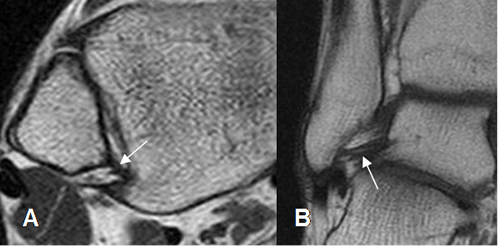

Fig 17. Ligamento calcaneoescafoideo.

A: RM axial en T1 y B: RM sagital en T2. Ligamento hipointenso normal, entre el escafoides y el calcáneo.